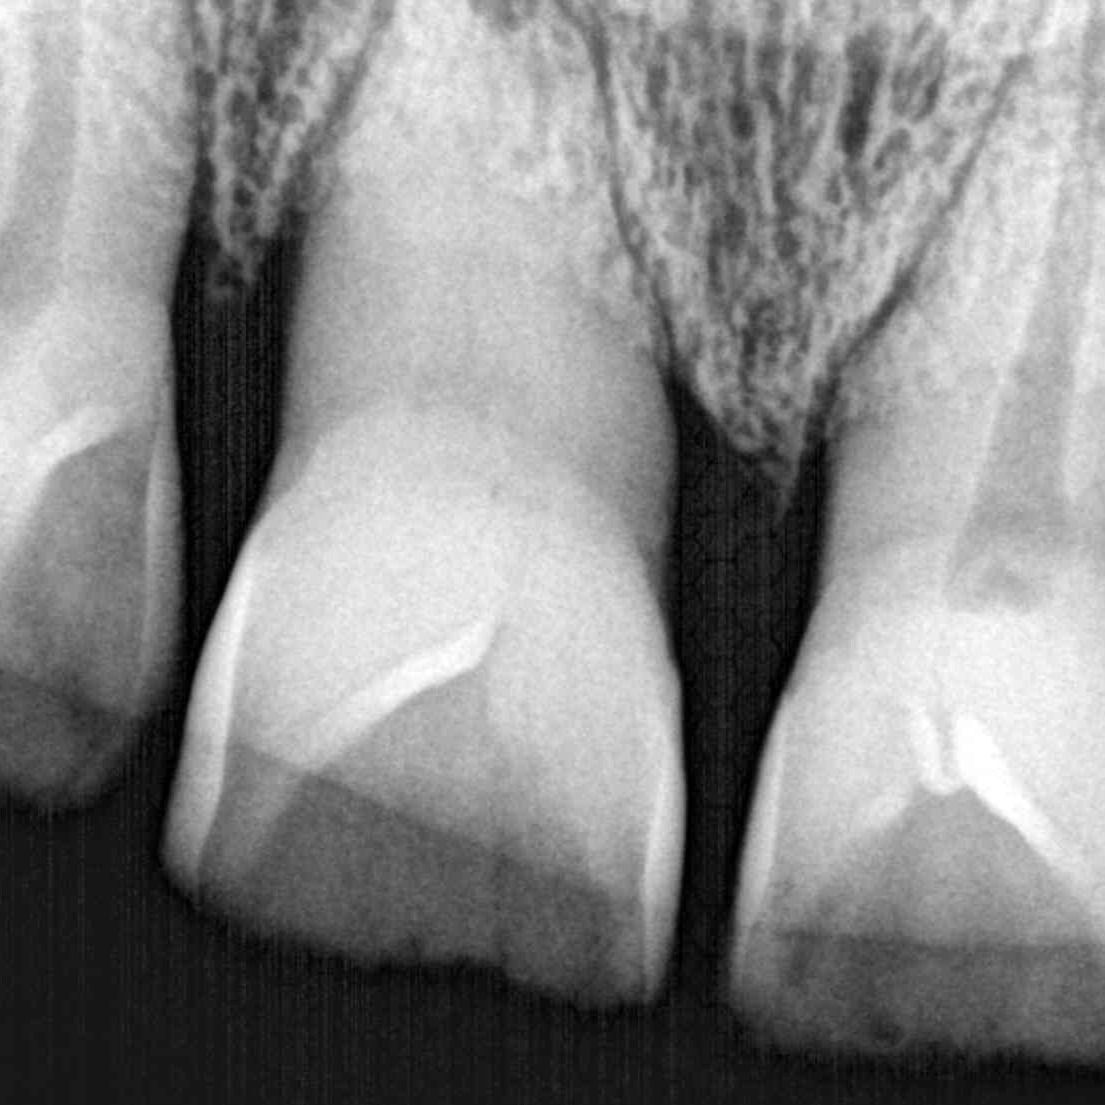

Los implantes sustituyen a los dientes perdidos, son raíces artificiales. Se introducen en el hueso maxilar y se dejan cicatrizar durante unas semanas.

Esta técnica es minimamente invasiva, ya que planificamos todos los casos con nuestra radiografía en 3 dimensiones y nuestro escáner intraoral.